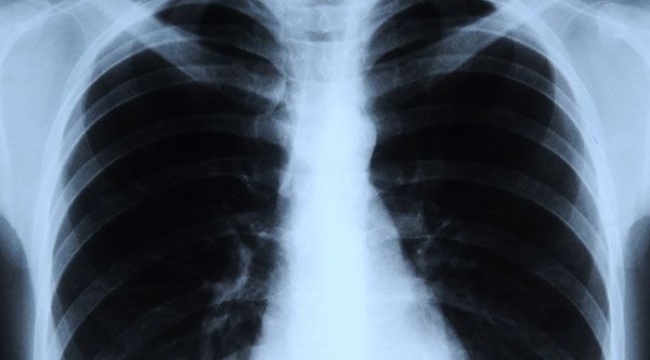

Vice haber sitesi bulguların “son derece endişe verici” olduğunu yazdı. Haberde, tıbbi algoritmaların farklı ırklardan hastalar için farklı sonuçlar verdiği önceki çalışmalar hatırlatıldı. Örneğin Aralık 2021'de yayımlanan bir çalışma, siyah ve kadın hastaların, doğru tanı alan ihtimalinin daha düşük olduğunu ortaya koymuştu. Araştırmacılar da ırkı doğru tahmin edip buna dayalı olarak farklı sonuçlar veren algoritmaların ortaya çıkmasından endişeleniyor.

Tıbbi görüntü analizine dahil olan tüm geliştiricilerin, düzenleyicilerin ve kullanıcıların derin öğrenme modellerinin kullanımını son derece dikkatli bir şekilde düşünmelerini şiddetle tavsiye ediyoruz. Çünkü bu tür bilgiler tıbbi uygulamada var olan ırksal eşitsizlikleri sürdürmek veya daha da kötüleştirmek için kullanılabilir.

Araştırma ekibinden Marzyeh Ghassemi "Öğrencilerim bana bu makaledeki bazı sonuçları gösterdiğinde, aslında bunun bir hata olması gerektiğini düşündüm." diye konuştu.